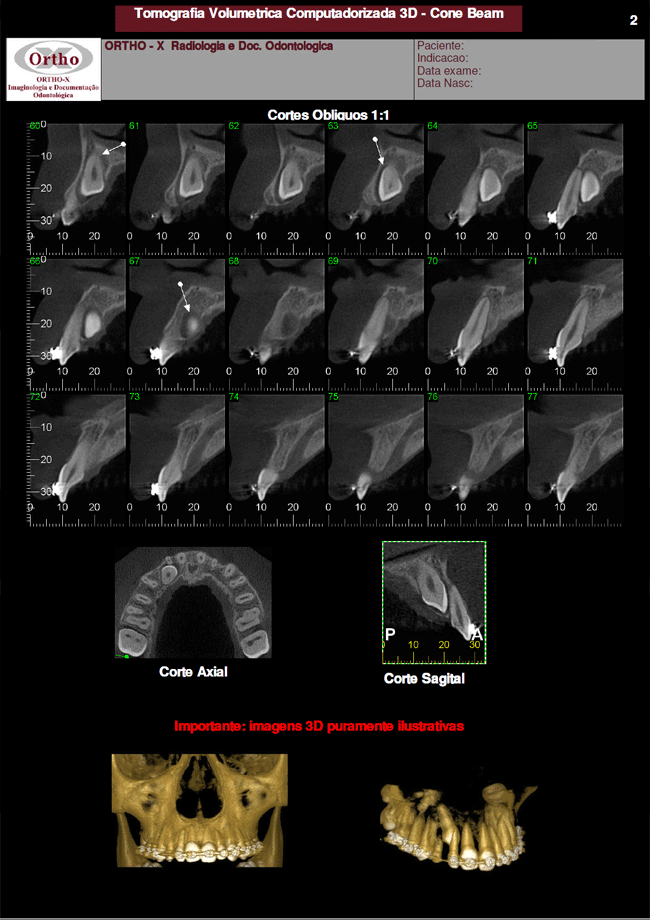

Exemplo de Exames: Dente Incluso